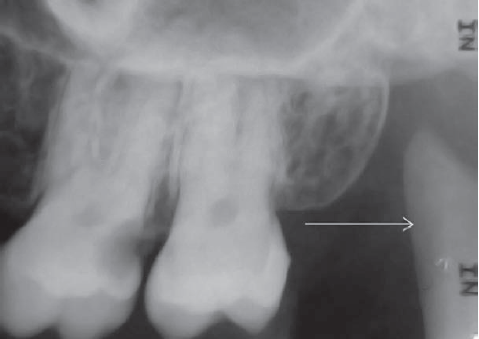

60. What is showing by arrow?

Submandibular Gland Fossa a bone depression on the lingual surface of the mandibular body, immediately below the mylohyoid ridge in the molar area. often appears as a radiolucent area with the sparse trabecular pattern